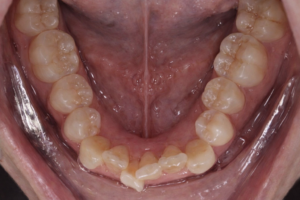

また、文献的にははっきりとした報告は少ないですが、第二大臼歯が外側にずれてしまうなど、咬み合わせへの影響が出る症例が多いと、個人的には感じています。

↑ 保定観察中に親知らずに押されてしまい、第二大臼歯が外側にずれる症例を経験しています